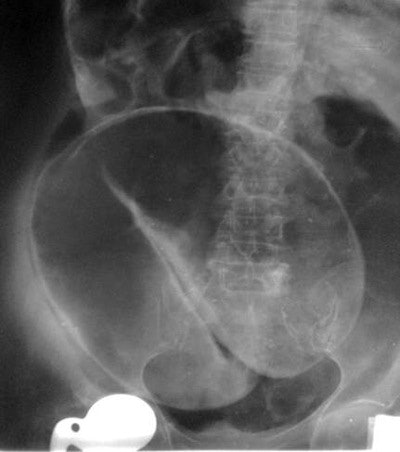

Coffee bean: This characteristic sign of sigmoid volvulus consists of a greatly distended, air-filled loop of sigmoid colon extending from the pelvis on abdominal radiography. The medial walls of the dilated bowel form a distinct oblique line that resembles the cleft of a coffee bean. It arises from the pelvis and may be large, with its apex often extending above the level of T10 to the left or right of the midline.